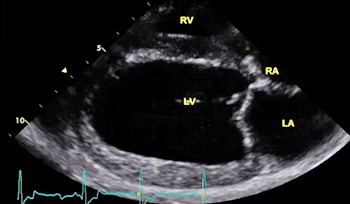

The echocardiograph examination shows the dimensions of the heart chambers, wall thickness and movement, valve movement and lesions, fractional shortening, among other characteristics. The echo screen shows the amount of wall contraction, which enables the operator to determine contractility, preload*, and afterload*. These factors are used to calculate "fractional shortening" (FS%) which is used as an indication of ventricular performance and of myocardial contractility.

(In the image at right, the red spurt of blood is shooting upward and backward, from the left ventricle, through the not-fully-closed mitral valve, back into the left atrium.)